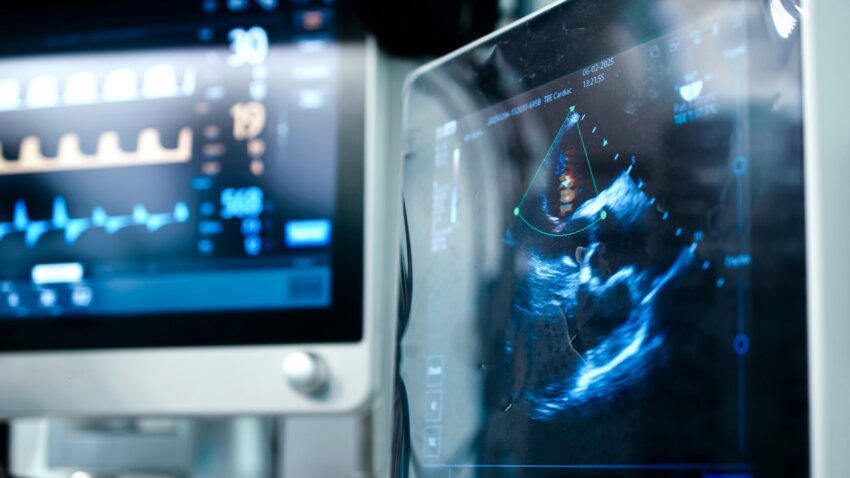

Because of its portability and safety, POCUS devices have become essential to how clinicians diagnose and treat patients, so much so that many medical professionals refer to it as the “stethoscope of the 21st century,” said Nilam Soni, MD, SFHM, FACP, professor of medicine and director of Critical Care Ultrasound Education at the Long School of Medicine, and director of the VA Point-of-Care Ultrasound Training Program for the Department of Veteran Affairs.

Soni explained that POCUS is often the go-to bedside tool for evaluating patients because the devices are small and portable, making it a much quicker diagnostic imaging option, and because it allows clinical decision-making at the bedside with the patient.

POCUS also improves procedural safety by allowing clinicians to visualize procedures like inserting a needle in real time.